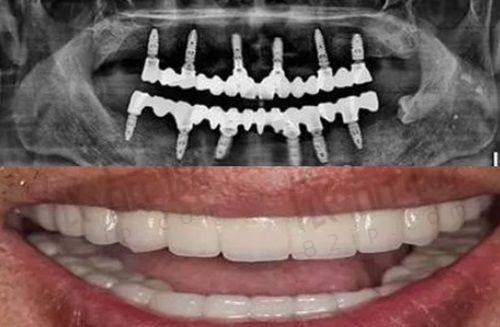

贵阳博尔佳口腔门诊部提供齐全的口腔诊疗服务,涵盖了牙齿修复、种植牙、牙齿美白等多个方面。牙齿修复可以帮助那些牙齿有缺损、缺失的患者修复牙齿的正常功能和美观;种植牙为牙齿缺失的患者提供了一种较为理想的修复方式,让患者能够重新拥有接近自然牙齿的咀嚼功能;牙齿美白则满足了人们对牙齿美观的需求,让笑容更加灿烂。

综上所述,贵阳博尔佳口腔门诊部是一家靠谱的口腔医疗机构。它成立于2021年,经过相关部门批准,提供齐全的口腔诊疗服务,包括牙齿修复、种植牙、牙齿美白等。其地理位置优越,交通便利,方便患者前来就诊。而且它还上榜了多项口腔医院名单,在上门牙埋伏牙手术和牙龈根部发黑等口腔疾病的治疗方面得到了行业的认可。去过的客人对其技术水平、服务态度和设备都给予了较好的评价。